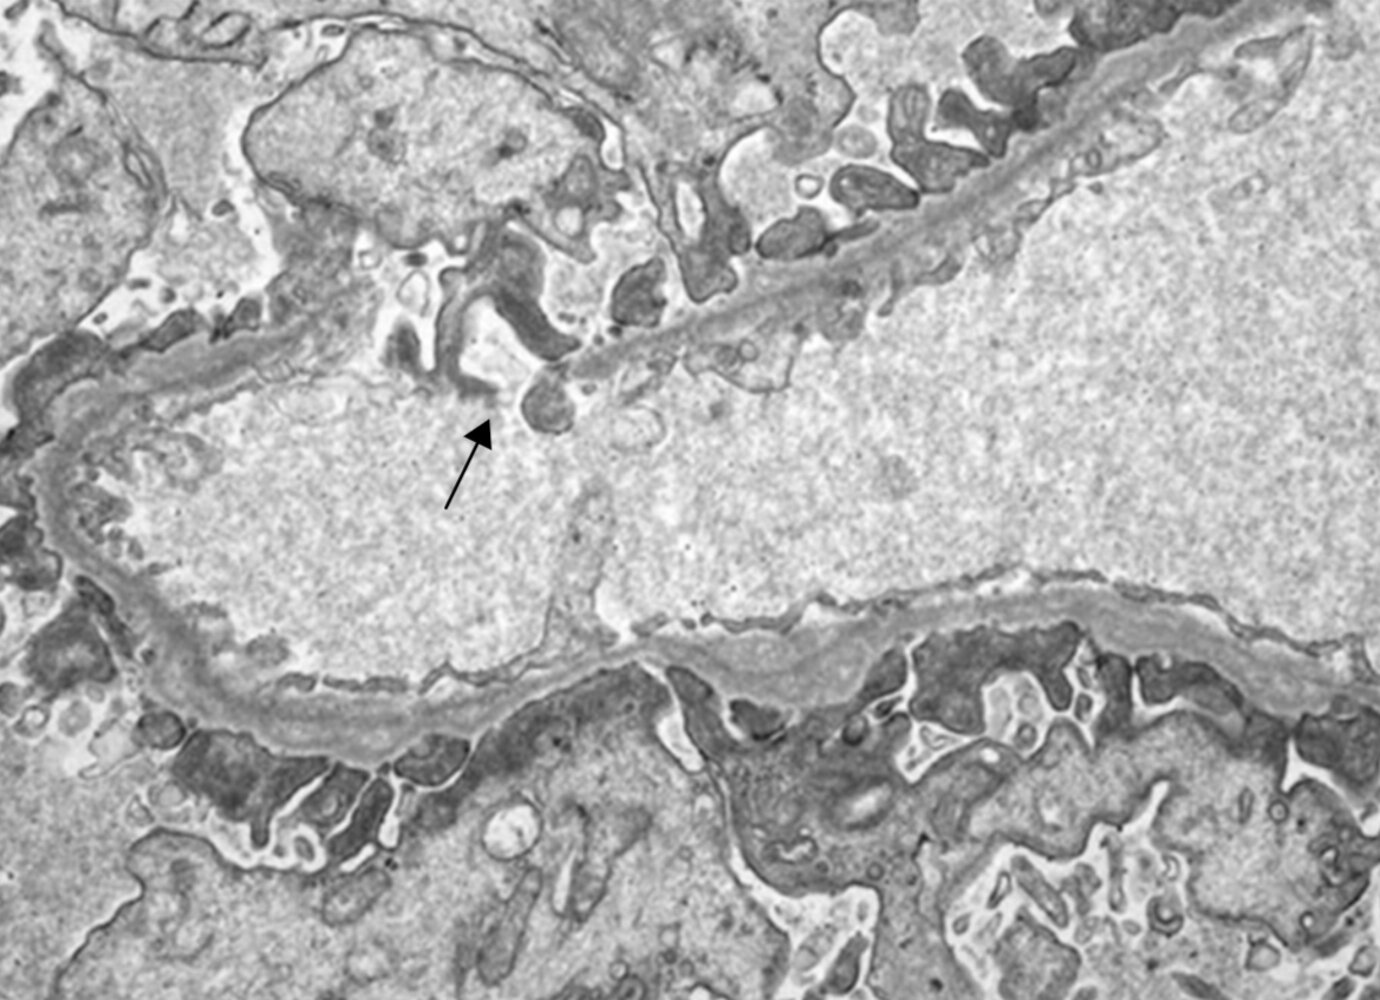

• Electron microscopy: splitting and alternating irregular thickening and thinning of the glomerular basement membrane (“basket-weave appearance”)